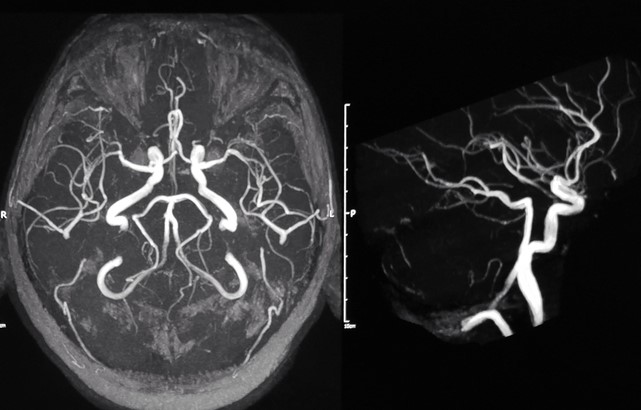

An ischaemic stroke is a type of stroke caused when an artery supplying blood to the brain is blocked by a blood clot. Without treatment, it can lead to long-term damage to the brain.